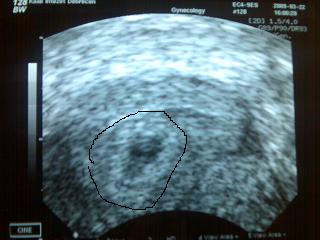

10mm-es petezsák, tuti van benne babó, volt vmi pulzálás, látta a doki a szikhólyagot, azt mondta, hogy 5-6 hetes lehet. 2 hét múlva megyünk oda utoljára, szívhangkukucsra. :D

Íme Babóca:

Amúgy a doki nagyon aranyos volt, mondta amikor közelített felém az uh-s cuccal, hogy akkor ő most vmi nagyon jót akar nekem mondani...bedugta, nézelődött és azt mondja: "10mm-es petezsák jó lesz?" :D Mondom elég jó. :D És akkor még sorolta, hogy biztos nem üres, látja benne a babót meg a szikhólyagot (jó szeme van :lol: ), meg vmi pulzálást emlegetett...de ez még nem a szíve. Jövő hét végefelé mehetnénk vissza uh-ra még...de a páromnak a péntek nemigazán jó, ezért mennénk inkább 2 hét múlva...és akkor majd elbúcsúzunk mindkét dokitól, a Kaálistól is meg az endo-stól is. A páromat uh után hívta be a nővérke, ogy akkor jöhet lefotózhatja a babót.